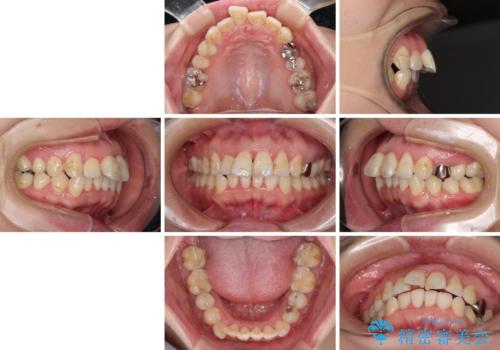

- 出っ歯と口の閉じにくさ、デコボコを気にして来院された患者様です。

口元の突出感を改善するため、上下左右第一小臼歯4本の抜歯を行い、ワイヤー装置による矯正治療を行うこととしました。

上下前歯の距離が大きかったため、上下の歯が接触するまでに時間がかかりました。

それでも目安である2年半で終えることができ、患者様には大変満足していただけました。